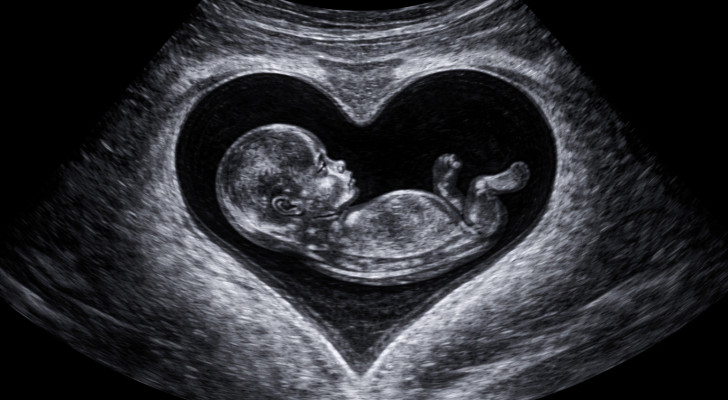

رحم على شكل قلب

الرحم الطبيعي يشبه الكمثرى، بينما الرحم ذو الشكل القلبي يظهر فيه تجويف الرحم مقسوم جزئيا أو كاملا إلى جزئين، مما يمنحه شكلا يشبه القلب عند النظر له عبر الأشعة التصويرية مثل السونار أو الرنين المغناطيسي. هذه الحالة غالبا تكون خلقية، أي موجودة منذ الولادة.